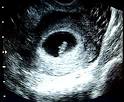

Enceinte de 7 semaines d amenorrhee

Enceinte depuis maintenant mois, la fatigue est toujours l, tout comme vos nauses. Images correspondant enceinte de semaines daposamnorrhe Entre et semaines d amnorrhe, soit entre et semaines de grossesse, la future maman vit son 2me mois de grossesse. Vos petit malaises persistent (manque d apptit, ballonnements). semaines de grossesse - Journal des Femmes janv. Alors que bb arborait jusque-l la forme d une virgule, voil que tout se prcise. Ma grossesse - 7e semaine d amnorrhe.

La semaine de grossesse (SA 7) - m La 5me semaine de grossesse : 7me semaine d amnorrhe. Grossesse: 7me semaine d amnorrhe : symptmes, traitement. On commence mme distinguer sa mchoire infrieure. 5e semaine de grossesse La 5e semaine de grossesse correspond SA (semaines d amnorrhe).